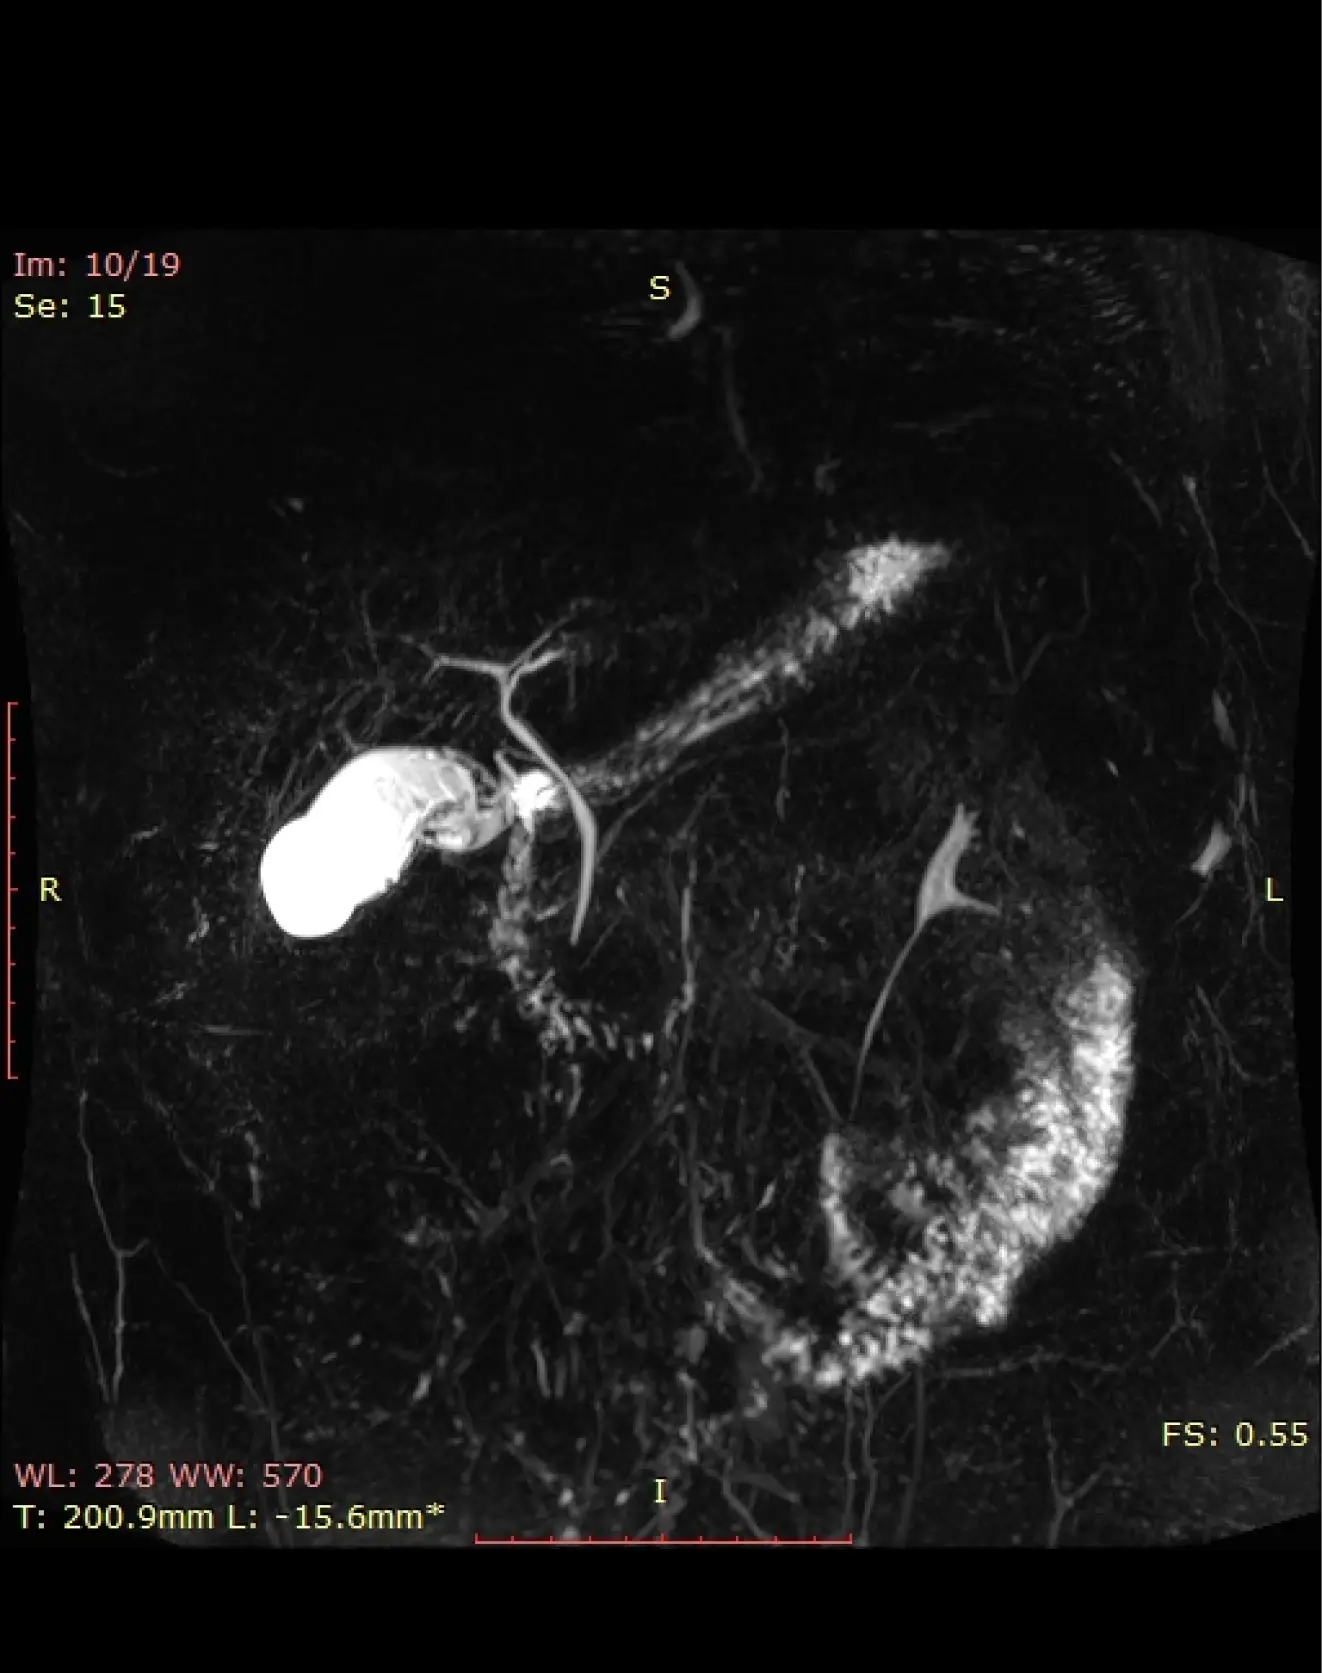

МРХПГ (MRCP)

Бесконтрастная визуализация полости желчного пузыря, внутри и внепеченочных желчных протоков, протока поджелудочной железы.